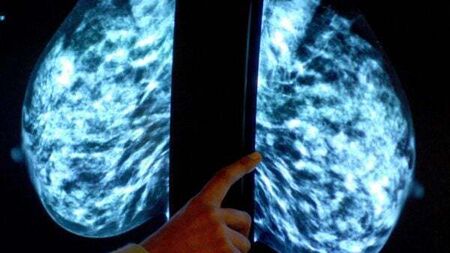

It was claimed the HSE allegedly failed to provide appropriate care for Ms Halligan, and that there had been an alleged failure to carry out an appropriate triple assessment of a mass on her right breast, including a biopsy when she was assessed at the Breast Clinic at University Hospital Waterford on June 4th, 2014.

There was, it was further claimed, a delay in the treatment of Ms Halligan’s breast cancer, and there was an alleged failure to refer Ms Halligan for a breast MRI scan after an irregular lump was recorded on June 4th, 2014, and noted by a consultant surgeon as suspicious for cancer and probably malignant.